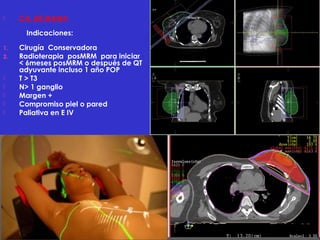

 CA. DE MAMA

Indicaciones:

1. Cirugía Conservadora

2. Radioterapia posMRM para iniciar

< 6meses posMRM o después de QT

adyuvante incluso 1 año POP

 T > T3

 N> 1 ganglio

 Margen +

 Compromiso piel o pared

 Paliativa en E IV